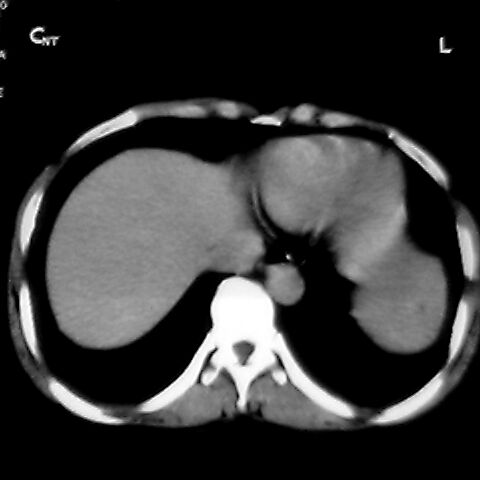

女 48岁 食道癌术前体检发现脾占位。

脾胀内部巨大低密度肿块,边界清或不清,中心坏死,轻度增强,内见散在钙化,结合食道癌病史多考虑:转移癌.

脾脏低密度灶伴钙化,增强化明显,中心见液化坏死灶,强化延时明显。考虑血管瘤。转移瘤待排。

1肝右下叶小囊肿2右肾上极囊肿或错构瘤3脾脏不典型血管瘤可能性大.